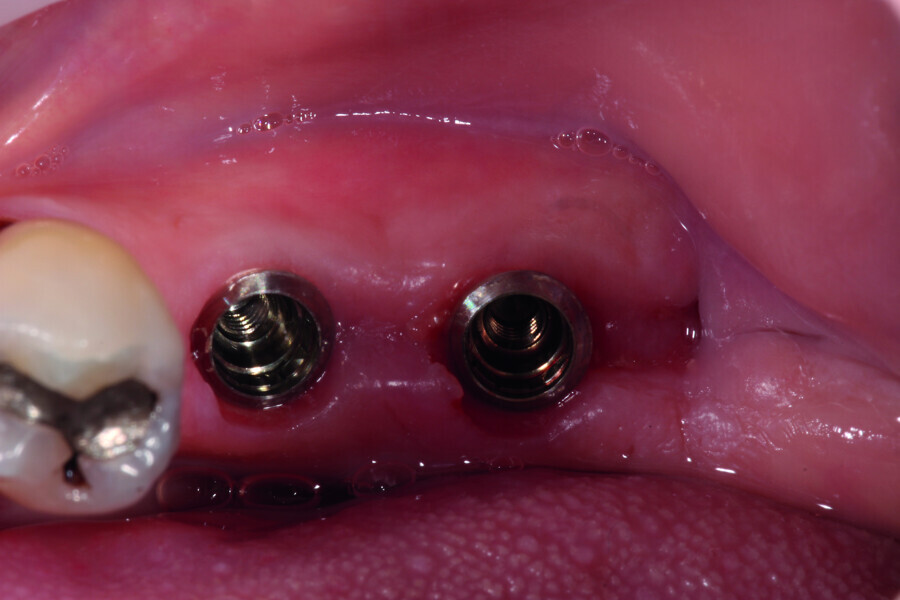

Digitising your implant practice